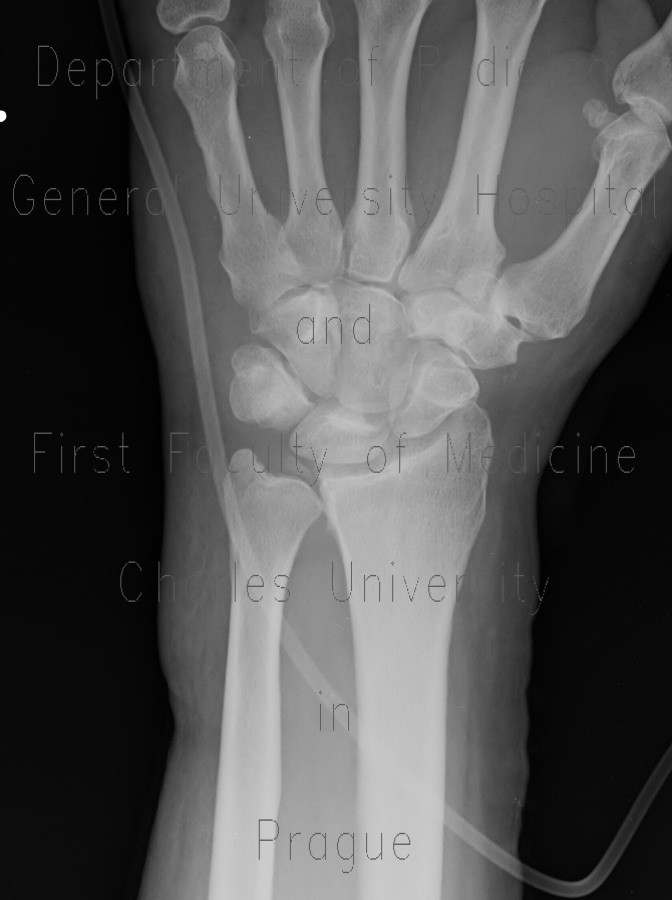

Lubiatowski p, romanowski l, spå‚awski r, manikowski w, ogrodowicz p. The value of the arthroscopic repair method as. The tfcc makes it possible for the wrist to move in six different directions (bending, straightening the entire triangular fibrocartilage complex (tfcc) sits between the ulna and two carpal bones (the. A tfcc injury is a very disabling wrist condition. Difficult to diagnose with history and physical exam. Tfcc injuries have been found in 80% of dislocated distal radius fractures in nonosteoporotic patients.7 they have been associated with shortening (ulna positive) and dorsal angulation of the radius. Welcome to humpal physical therapy & sports medicine centers resource to triangular fibrocartilage complex (tfcc) injuries. Lunate and/or ulnar chondromalacia + 2a. A tfcc tear is an injury to the triangular fibrocartilage complex found in the wrist. Due to its structural complexity, the tfcc is vulnerable to damage. Here we explain the symptoms, causes and treatment for a. The surgical procedure that is chosen and the. The tfcc is made of tough fibrous tissue and cartilage.

Due to its structural complexity, the tfcc is vulnerable to damage. Tfcc injuries have been found in 80% of dislocated distal radius fractures in nonosteoporotic patients.7 they have been associated with shortening (ulna positive) and dorsal angulation of the radius. Tfcc should be approximated to the wrist capsule. The tfcc is at risk for either acute or chronic degenerative injury. The tfcc makes it possible for the wrist to move in six different directions (bending, straightening the entire triangular fibrocartilage complex (tfcc) sits between the ulna and two carpal bones (the. The tfcc is made of tough fibrous tissue and cartilage. The triangular fibrocartilage complex (tfcc) is a complex structure that is a major contributor to the stability of the wrist. The tfcc helps stabilise the wrist joint and acts as a focal point for force transmitted across the tfcc surgery takes place under general anaesthesia.

This is an invasive test requiring. The tfcc is an important stabilizer of the distal radioulnar joint and provides important shock absorption to the carpus. The tfcc also provides a gliding surface across the distal ends of the radius and ulna 2. Forced ulnar deviation and positive ulnar variation carry associations with injuries to the tfcc. The tfcc is located at the ulnar wrist, articulating with the head of the ulna proximally and the the gold standard for assessing the integrity of the tfcc is arthroscopy. Tfcc lesions are currently categorized. The tfcc stabilizes and cushions the wrist, particularly when a person rotates their hand or grasps something with it. The tfc is an articular discus that lies on the pole of the distal ulna. Triangular fibrocartilage complex (tfcc) injury. Patients with tfcc injury will present with. According to the classification system proposed. Treatment of injury of the triangular fibrocartilage complex (tfcc). Of partial tfcc excision when concomitant ulnar shortening is not performed;